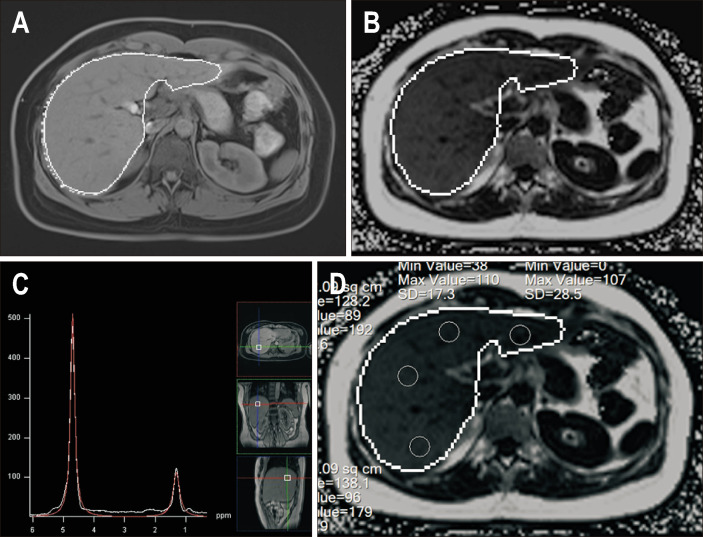

Background/aims: Magnetic resonance imaging (MRI) with a proton density fat fraction (PDFF) sequence is the most accurate, noninvasive method for assessing hepatic steatosis. However, manual measurement on the PDFF map is time-consuming. This study aimed to validate automated whole-liver fat quantification for assessing hepatic steatosis with MRI-PDFF.

Methods: In this prospective study, 80 patients were enrolled from August 2020 to January 2023. Baseline MRI-PDFF and magnetic resonance spectroscopy (MRS) data were collected. The analysis of MRI-PDFF included values from automated whole-liver segmentation (autoPDFF) and the average value from measurements taken from eight segments (avePDFF). Twenty patients with ≥10% autoPDFF values who received 24 weeks of exercise training were also collected for the chronologic evaluation. The correlation and concordance coefficients (r and ρ) among the values and differences were calculated.